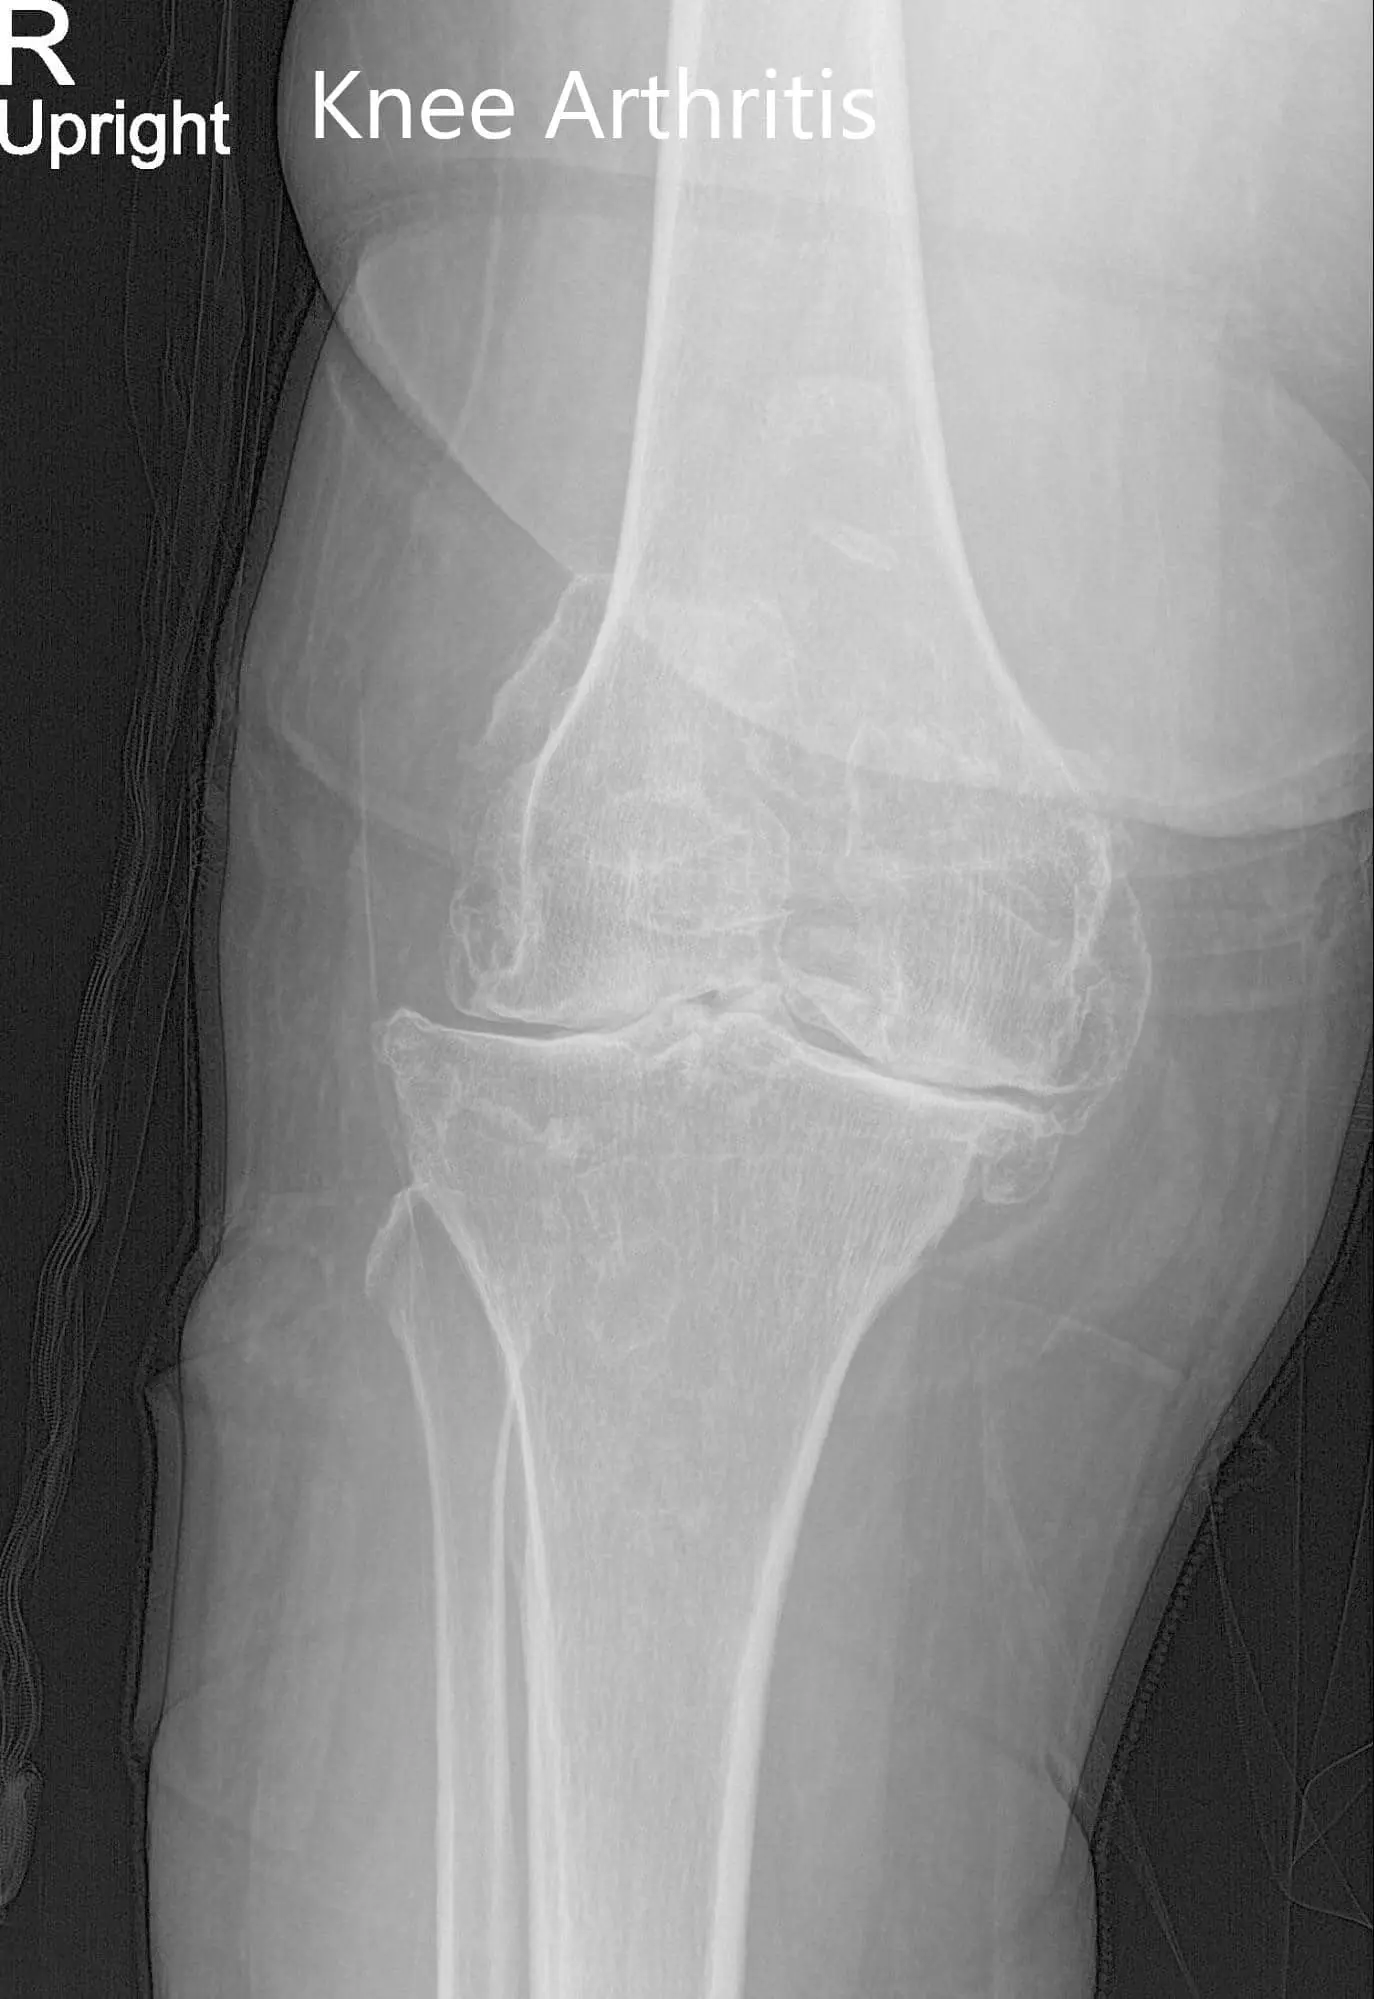

Preoperative X-ray of the right knee showing AP and lateral views